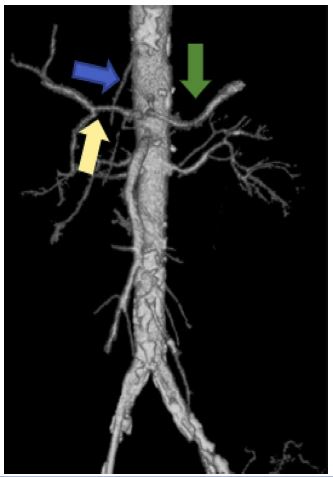

363 out of 388 cases showed a normal trifurcation pattern of the coeliac trunk (Uflacker I) representing 93.5 % of the total cases. Among the commonest anomalies among the coeliac, trunk variations were Type V Uflacker in the form of the gastro-splenic trunk with CHA arising from the aorta (most common anomaly) (Figure 1) representing 20 % of cases followed by Uflacker types II, III, IV & VIII (Figure 2) each type found in 4% of cases.

Figure 1: Axial CT cuts showing gastrosplenic trunk (red arrow) with CHA (white arrow) separately arising from the aorta.

Figure 2: Volume-rendered image showing the separate origin of CHA (Yellow arrow), LGA (Blue arrow) & Splenic artery (Green arrow) from the aorta.